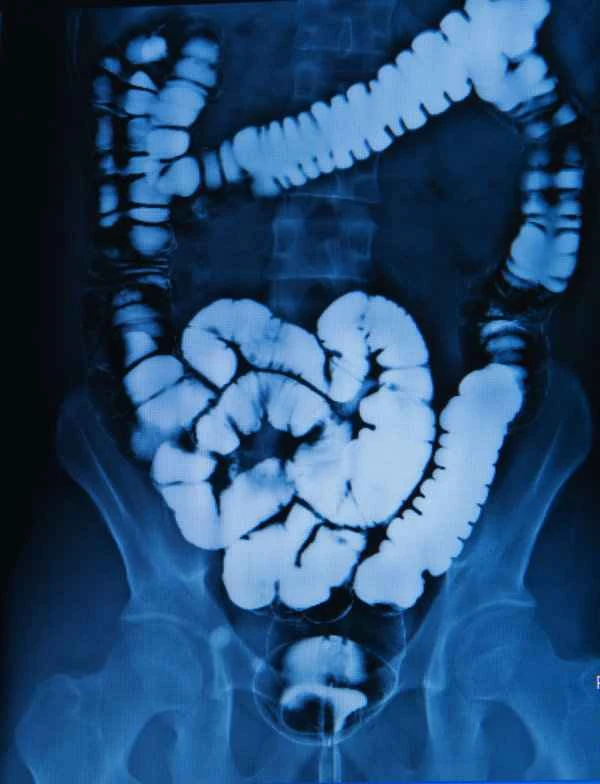

Duodenal obstruction is a digestive system disorder that occurs in the duodenum (the first part of the small intestine), preventing the proper passage of food and fluids. Causes of obstruction can include tumors, inflammation, scar tissue, or congenital abnormalities. In some cases, the obstruction may be reversible, such as obstruction caused by inflammation or scar tissue, which may be relieved with medication or endoscopic treatment. When the obstruction is caused by irreversible disease factors, such as malignant tumors or severe scar tissue, surgical resection of the duodenum may be necessary. The purpose of surgical resection is to relieve obstructive symptoms and prevent complications such as malabsorption, infection, or perforation. The decision to perform resection requires comprehensive consideration of the patient's clinical presentation, imaging findings, and pathological examination results.

When deciding whether to perform surgical resection, doctors consider a variety of factors, including the cause, location, and severity of the obstruction, as well as the patient's overall condition. For example, if the obstruction is caused by a malignant tumor that has invaded the duodenum, surgical resection may be the only option. If the obstruction is caused by a benign condition, such as inflammation or scar tissue, doctors may first try non-surgical treatments, such as medication or endoscopic procedures. In some cases, if non-surgical treatments are ineffective, or if the patient develops serious complications, such as malabsorption or infection, surgical resection may be necessary. Whether duodenal resection is required depends on the specific circumstances.